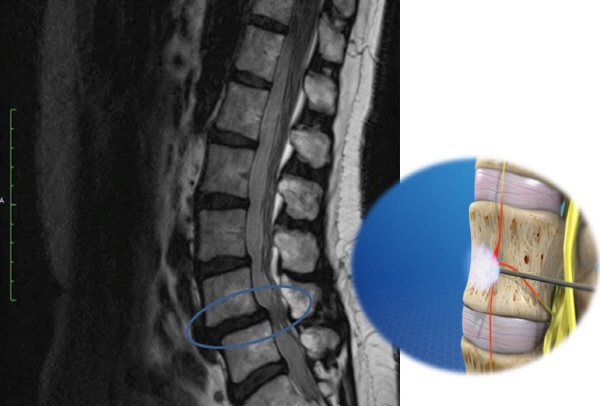

척추관 협착증이란 척추 중앙의 척추관, 신경근관 또는 추간공이 좁아져서 허리의 통증을 유발하거나 다리에 여러 복합적인 신경 증세를 일으키는 질환을 뜻합니다.

척추관이란 척추 가운데 관 모양의 속이 빈 곳으로 아래 위 척추에 의해 추간공이 생기며 가운데 관 속은 뇌로부터 팔다리까지 신경(척수)이 지나가는 통로가 됩니다.

허리 디스크와 다르게 척추관 협착증은 허리통증 보다는 다리 저림이나 당김 증상이 있어 보행에 가장 큰 어려움을 느낄 수 있습니다. 그래서 오래 걷기가 힘들고 오래 걷지 않았음에도 자꾸 주저앉게 되는 경우가 있는데 전형적인 협착증의 증상이라 할 수 있습니다. 근본적으로 요추부(허리)의 문제 이긴 하지만 허리디스크와 달리 허리 통증이 항상 동반되지는 않으며 있더라도 허리디스크에 비해 적은 정도의 통증이 나타나게 됩니다.

허리를 앞으로 숙이면, 척추관이 넓어지기 때문에 허리를 숙이고 있거나 앉아있는 것이 편안하게 느껴집니다. 허리를 펴고 오래 걷거나 서있기 어려우며 100~200m 이상 걸으면 다리에 힘이 빠지거나 통증이 심해 자꾸 쪼그려 앉게 됩니다.